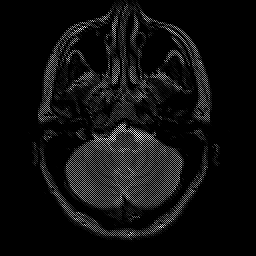

glioma overlay -- Slice #5

[Home][Help][Clinical] Slice 5